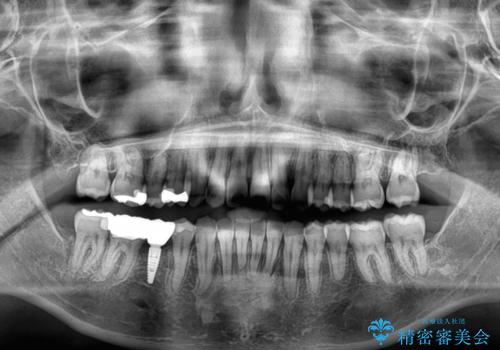

後方移動と同時上下歯列をワイヤー装置にて整え、奥歯の欠損部には矯正治療の途中でインプランを埋入していくこととしました。

上顎歯列全体を後方移動させたことで唇に当たる感覚は改善され、更には上下の正中位置も合わせることができました。